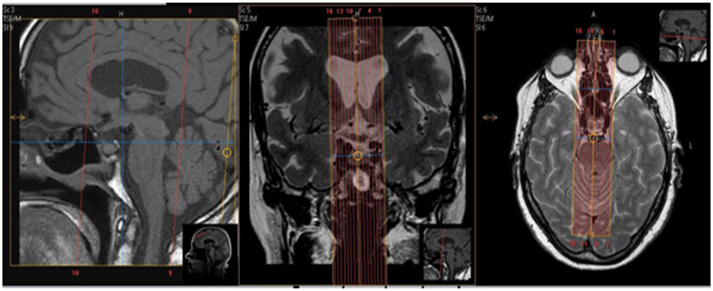

| SAG | T1 | TSE | 2mm | 0mm | None | 15cm | Pituitary only. Angle as usual. |

| COR | T1 | TSE | 2mm | 0mm | None | 13cm | Pituitary only. Angle as usual. |

| COR | T2 | TSE | 2mm | 0mm | None | 13cm | Pituitary only. Angle as usual. |

| AXIAL - No angle | T1 TSE | TSE | 2mm | 0mm | SPIR | 25cm | No Angle. Skull Base to Vertex. |